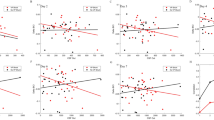

A total of 22 patients (13 males, 9 females) met the inclusion criteria. Mean age of the cohort was 4.9 years (range 0.1–18 years). CSF volume calculation was performed using the manual method and the automated algorithm on the entire cohort. Three different analysts (two neurosurgeons and the creator of the algorithm) repeated these measurements using both methods of analysis. Average measured CSF volume was similar between the manual and automated methods (169.8 mL vs 172.5 mL, p = 0.56). However, the automated algorithm performed this analysis significantly faster than the manual method (58.5 times faster, 38.3 s vs 2244 s, p < 0.01). The reproducibility between investigators and the two methodologies (manual and automated) was also evaluated. The correlation between the three examiners was > 99% (\(\pm\) 1.43%, range: 99.3 to 99.5%).

In all three of the presented cases, the automated volumetric analysis showed that the CSF ventricular volumes had increased since initial admission (41.7%, 43.8%, and 11.3%, respectively) (Table 1). This increase, however, was not definitively detected on routine interpretation by a neuroradiologist. Use of the novel algorithm would have detected these changes, therefore preventing the delay in the patients’ care.